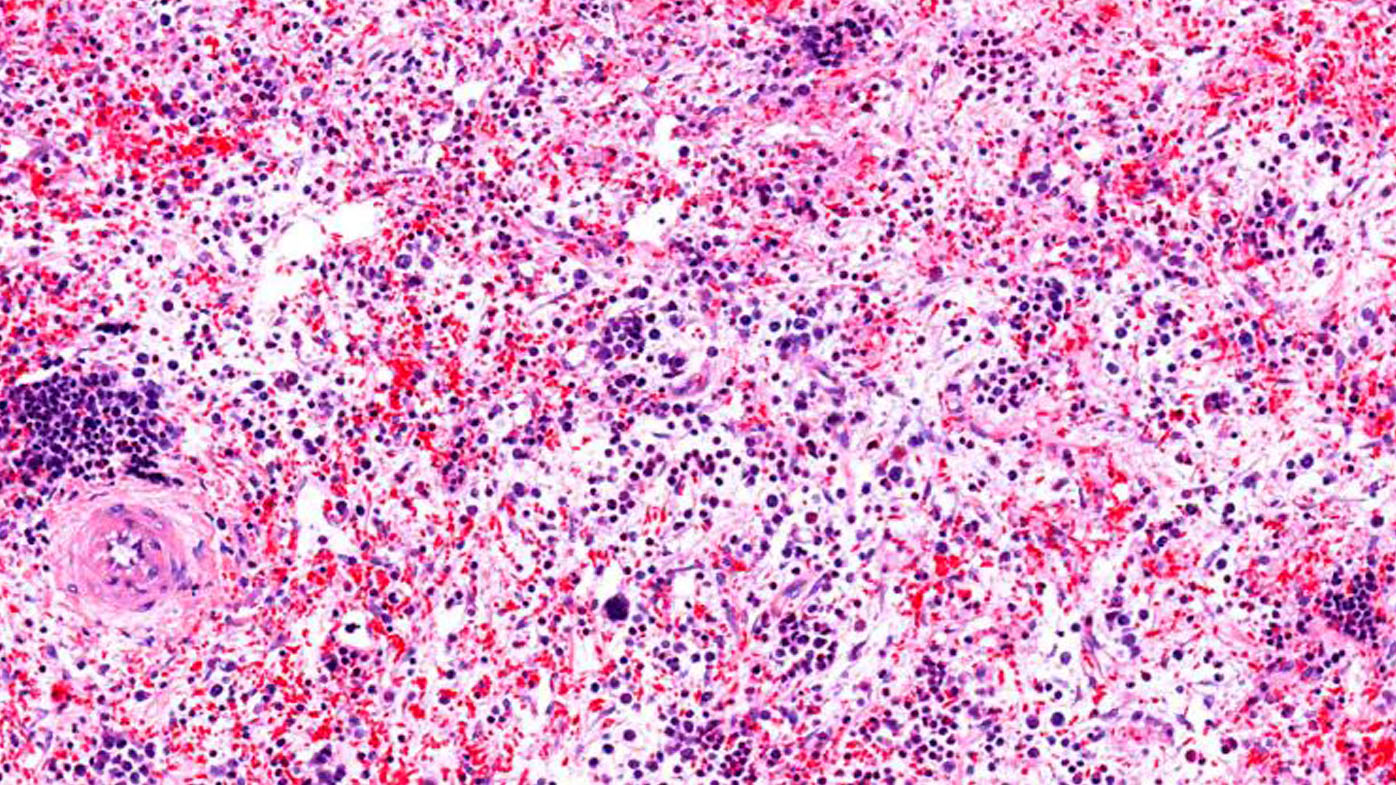

Similarly, the mutation sends blood cells at a pace beyond what the body can handle. This may lead to scarring in the bone marrow, an excess of abnormal white blood cells and too few functioning red blood cells.